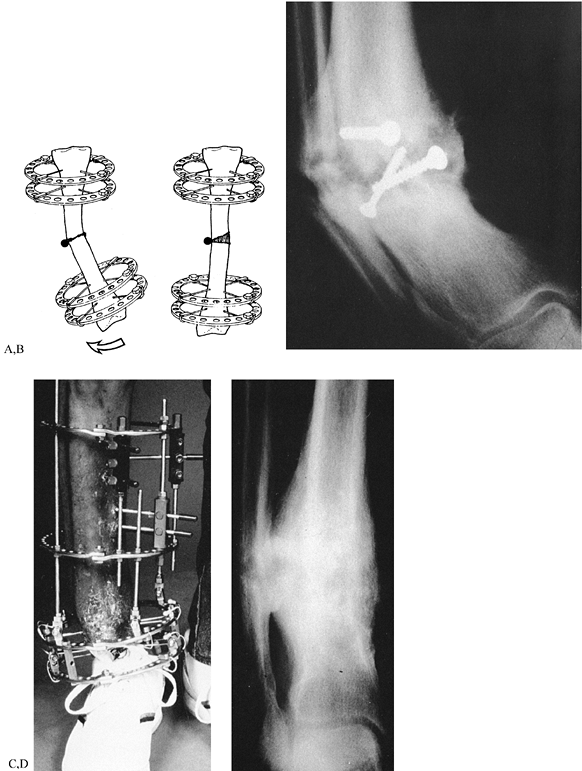

Figure 32.43. A:

Bilateral genu varum from varus deformities of both femurs and the right tibia. Both tibias have been previously operated on. The right tibia still has a varus deformity. The preoperative planning of the right side of this deformity was illustrated in Figure 32.23. B: A single level of osteotomy was chosen for both the tibia and the femur. One could justify two levels of osteotomy within each bone; however, since the amount of bowing in each bone was not severe, it was felt that this could be treated as a single apex angular deformity, recognizing that it truly was a multiapex angular deformity. Therefore, we chose to ignore the anatomic axis of the tibia and realign both the mechanical axis of the tibia and the joint orientation of the knee and ankle. This gives the patient a result similar to that achieved on the plated left side. The alternative would have been a combined proximal and distal tibial osteotomy, which would normalize both the anatomic and the mechanical axes of the tibia. An acute correction was performed in the femur at a level distal to the apex of the deformity, as described in Figure 32.23, to minimize the lateral indentation of the side that would result from a single-level, more proximal osteotomy at the apex. C: The result demonstrates complete realignment of the hip, knee, and ankle joint orientations, as well as the mechanical axis. On the opposite side, the osteotomy was performed slightly distal to the apex of the deformity and, therefore, a lesser amount of translation was needed. The result in terms of joint alignment and orientation is identical. |

The clue that there is more than one apex of angulation is that the

single center of rotation determined by the intersection of the

proximal and distal mechanical axis lines is at a level where there is

no “obvious” angulation (Fig. 32.44, step 1).

In multiapical deformities, there is usually one obvious (diaphyseal,

hip, or ankle) apex and one less obvious angulation apex. The obvious

apex should be corrected first. The apex of this level may be chosen

based on cortical or midbone lines, or, in the case of hip or ankle

deformities, we know the apex is at the center of the joint. Once the

first apex of angulation is corrected, it will point to the second apex.

malalignment, correct it together with the tibial or femoral varus

angulation. With conventional techniques, the head of the fibula can be

osteotomized and moved distally. By the Ilizarov method, the proximal

fibula is pulled down to tighten (even overtighten) the lateral complex

(Fig. 32.15, Fig. 32.41).

The medial collateral ligament can also be tightened by distracting the

tibia through an osteotomy proximal to the insertion of the medial

collateral ligament. To tighten the medial collateral ligament without

pulling down the patellar tendon, direct the osteotomy of the tibia

obliquely, distally, and laterally, to exit below the tibial tuberosity

(Fig. 32.15).

opening wedge, dome, closing wedge, or angular displacement

osteotomies. Both distraction and conventional methods use all of these

osteotomy types. With conventional osteotomy, the correction is

achieved acutely in the operating room; stability is achieved with

internal or external fixation. The closing wedge technique is preferred

because of the good bone-to-bone contact possible. Conventional opening

wedge methods usually require a bone graft and have a higher incidence

of nonunion. The dome osteotomy is a compromise between the opening and

closing wedge, avoiding the length loss of the closing wedge method and

offering some adjustability. The complications with these techniques

include nonunion, osteomyelitis, compartment syndrome, nerve injury,

and vascular injury (6). Accuracy

of correction is often a problem, especially with the closing wedge

technique. Even with meticulous planning, factors such as x-ray

magnification, rotated x-rays, measurement error, the thickness of the

saw blade, and the expertise of the surgeon all contribute to

inaccuracy with conventional methods (19). After the operation, there is no nonoperative way to adjust incomplete correction (15,17).

accurate. Since Ilizarov’s technique is percutaneous, there is little

risk of compartment syndrome, nerve injury, vessel injury, nonunion, or

osteomyelitis. The correction is performed either acutely for small

deformities or gradually for larger deformities (25).

Gradual distraction prevents nerve stretch injuries, as can occur in

the correction of a valgus tibial deformity. The distraction method is

as accurate as one can measure on a radiograph, perhaps the greatest

advantage of Ilizarov’s technique. Even after acute corrections,

adjustments can be made to fine-tune the correction until the exact

alignment of the limb is achieved.

correct as frontal or sagittal plane ones. More complex deformities,

including rotation, translation, and limb-length discrepancy, can all

be managed simultaneously. Multilevel and multibone corrections can be

done since there is little blood loss and the apparatus can be applied

to multiple levels and bones simultaneously. Lengthening can be

performed for small and large discrepancies, as needed, at one or more

levels. Associated problems of nonunion, contracture, and osteomyelitis

can be treated at the same time. The apparatus allows for unrestricted

weight bearing and personal hygiene; weight bearing is usually

restricted with internal fixation, and bathing is difficult if a

protective cast is used.

related to external fixation, including wearing a bulky apparatus for a

prolonged period, pin infections, muscle transfixion, loss of joint

range of motion, and pain. With proper application of the device, the

last three problems should be minimal. More recently, with the use of

half

pins instead of transfixion wires, these problems have been significantly reduced.

advantageous in treating complex deformities. Nevertheless, it still

offers many advantages even for simple deformities that have a good

conventional alternative, such as high tibial osteotomy. The decision

to use Ilizarov’s distraction method rather than a conventional

osteotomy and fixation depends on all of these factors, not the least

of which is the surgeon’s experience in the application of the

distraction osteotomy.

using hinges consists of two levels of fixation proximal and two levels

distal to the apex of the deformity (Fig. 32.45).

Each level of fixation is perpendicular to either the anatomic or the

mechanical axis of the bone fragment to which it is affixed. The hinge

connects the proximal and distal blocks of fixation, articulating

between them at the desired center of rotation for correcting the

angular deformity (23).

![]() |

|

Figure 32.45. A:

Center of rotation hinge apparatus. There are two levels of fixation in each bone segment on opposite sides of the osteotomy. The rings are applied perpendicular to their respective bone segment. The hinge lies perpendicular to the ring. In this example, the hinge is applied over the apex of the deformity, with the hinge rod overlying the medial convex cortex of the tibia. On the concave aspect, there is a distraction rod connected by two twisted plates and a suspending post. The post connection to the twisted plate allows for self-adjustment of the distraction rod angle to that of the ring. B: After the correction is completed, all the rings are parallel and the hinge rods are colinear. Notice the open-wedge correction of the tibia and fibula and the change in angle between the distraction rod and the ring. C: For a juxtaarticular deformity of the tibia, the apparatus employs a translation hinge. Notice that the hinge is located over the level of the tibial physis. This is proximal to the upper ring. Two levels of fixation were achieved in each bone segment on opposite sides of the osteotomy. D: At the end of the correction there is an angulation and translation of the bone segments at the level of the osteotomy. The rings are now parallel and the hinge rod is straight. Notice again the change in orientation of the distraction rod to the rings. |

the convex side, then distraction of the concavity will lead to an

opening wedge correction (Fig. 32.34, Fig. 32.46A).

If the hinge is placed at a distance from the convex side of the apex

of the deformity, then lengthening will occur together with correction

of angular deformity (Fig. 32.46B, Fig. 32.47). Placing the hinge on the concave side of the deformity will lead to compression of the bone ends with angular correction (Fig. 32.46C, Fig. 32.48).

If the hinge is placed either proximal or distal to the level of the

osteotomy, then translation of the bone ends will occur with angular

correction during distraction of the concavity (Fig. 32.46D, Fig. 32.49).

Figure 32.46. A:

Opening wedge hinge. The hinge is located at the level of the osteotomy overlying the convex cortex of the bone. Distraction of the concavity leads to an opening wedge correction without separation of the convex cortices of the bone. B: Distraction hinge. The hinge is located away from the convex cortex of the bone but still at the level of the osteotomy. Distraction of the concavity leads to simultaneous lengthening with angular correction. The regenerate has the appearance of a trapezoid, with a wider separation on the concave side than on the convex side. C: Compression hinge. If the hinge is located at the level of the osteotomy but on the concave side of the bone, distraction of the concavity will lead to compression of the bone ends. If the bone ends allow, this will produce a closing wedge type of correction. D: Translation hinge. If the hinge is located proximal or distal to the level of the osteotomy, distraction of the concavity will lead to translation of the bone ends. In this example, the hinge is located at the intersection point of the convex cortices of the two bones and, therefore, distraction of the concavity leads to correction of the angulation and translation of the bone ends. |

Figure 32.47. Application of distraction hinges for lengthening and correction of deformity. A:

A 5-year-old girl with bilateral genu varum and shortening due to meningococcemia septic emboli. She has skin grafts adherent to the bone and, therefore, distraction must be performed very gently. B: Standing radiographs show the deformities and the preoperative planning markings for the placement of olive wires. C: The apparatus has a hinge located lateral to the convex aspect of the osteotomy. To augment the stability of the fixation, the distal hinge has a threaded rod applied through the center of the anterior and posterior hinge point. This can be performed only with distraction hinges. D: Toward the end of the correction, notice the increased length achieved through the distraction hinges without lengthening on the hinge rods. All of the lengthening is performed by distraction of the concavity. Notice that this method is gentle on the skin and there were no skin problems. E: The final radiographs demonstrate 8 cm of lengthening of both tibias with realignment. Notice the bilateral triangular shaped tali. Both feet were plantigrade at the end of the correction. F: The final appearance of both legs at the end of the lengthening and correction of deformities. |